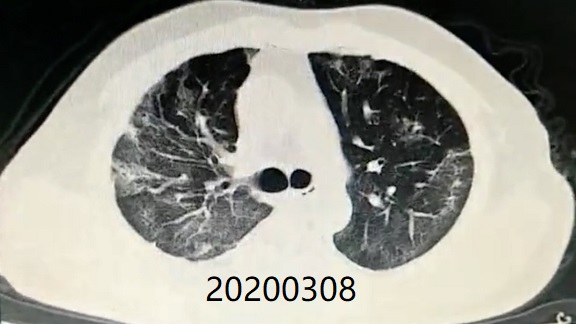

Comparison of CT imaging of chest before and after treatment with the patient (Mr. Zhang)